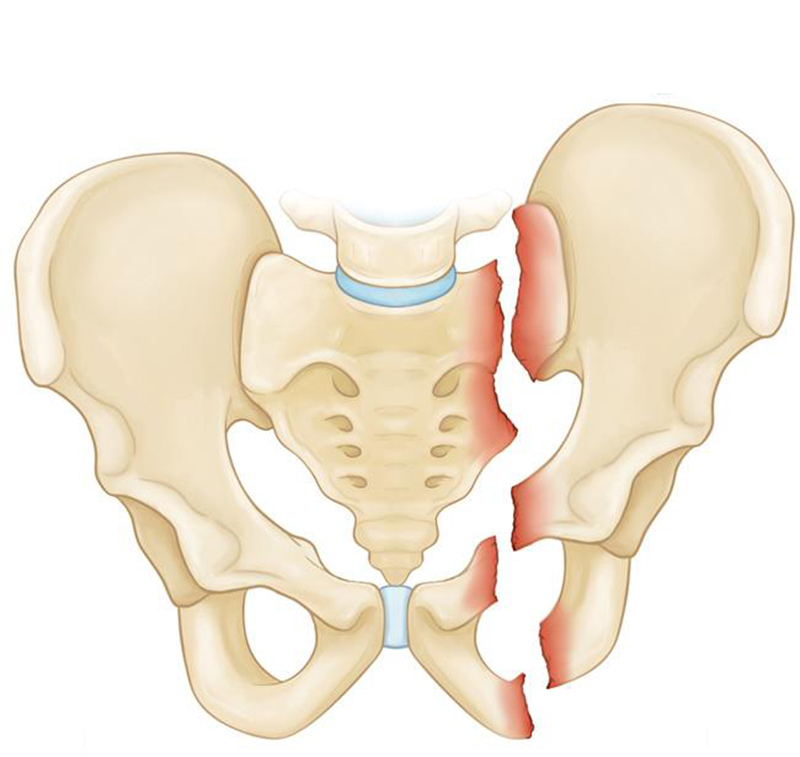

تعویض مفصل لگن که به آن آرتروپلاستی لگن نیز گفته می شود، یک روش جراحی برای رفع درد لگن است. در این جراحی قسمت هایی از مفصل لگن با ایمپلنت مصنوعی جایگزین می شود. مفصل لگن از یک توپ (در بالای استخوان لگن ، که به عنوان استخوان لگن نیز شناخته می شود) و یک حفره (در لگن که به عنوان استخوان لگن نیز شناخته می شود) تشکیل شده است. جراحی تعویض مفصل لگن شامل تعویض یک یا هر دو قسمت است. هدف از این روش این است که به شما امکان می دهد فعالیت های روزانه و ورزش را با درد کمتر از سر بگیرید.

- آسیب هایی مانند شکستگی لگن

در طی تعویض کامل مفصل لگن (آرتروپلاستی کامل هیپ)، هم توپ و هم سوکت تعویض می شوند. تعویض جزئی لگن فقط توپ را جایگزین می کند (سر استخوان لگن ).